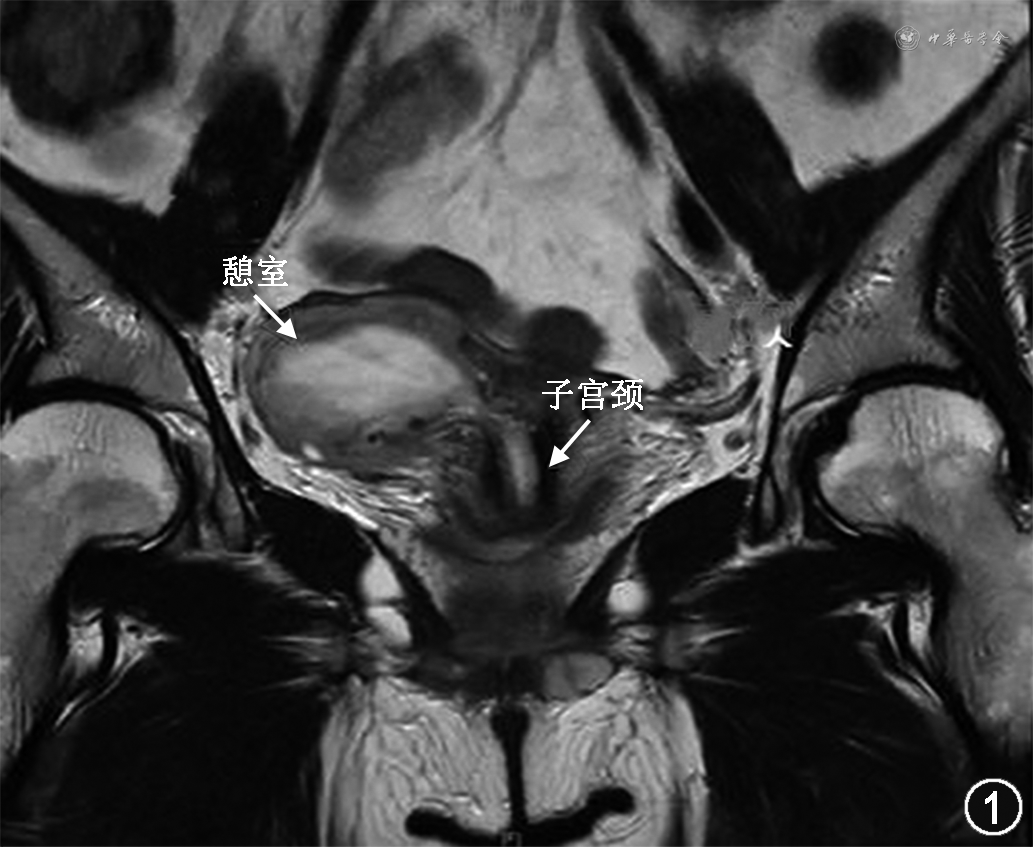

9月10日入院后,复查经阴道超声提示:子宫峡部右前壁探及向外突起的、边界清晰的低回声5.5 cm×5.6 cm×3.4 cm,其内可见形态不规则的不均质低回声,其内血流信号不丰富,考虑浆膜下子宫肌瘤变性可能。泌尿系统超声检查提示双侧肾、输尿管未见异常。盆腔MRI检查提示:子宫右前方浆膜下团块状混杂等T1长T2为主信号影,局部与宫腔相通,大小为4.7 cm×5.0 cm×4.6 cm。见图1。检测血清抗苗勒管激素水平为3.37 μg/L,提示卵巢储备功能正常。患者于9月14日在全身麻醉下接受了宫腔镜联合腹腔镜检查;腹腔镜检查见子宫后位,正常大小,活动好,子宫峡部右侧前壁可见囊性包块凸向阔韧带,直径6 cm,双侧输卵管外观未见明显异常、正常插入双侧宫角,双侧卵巢外观未见异常;转宫腔镜检查,逐步扩张宫口至10号扩宫棒,置镜见子宫颈管内可见两个开口,见图2,沿扩张后的右侧开口进入,见腔内囊壁粗糙,似被覆内膜样组织,伴活动性出血,此时腹腔镜下见宫腔镜操作位于子宫峡部前方包块内,退镜后,于腹腔镜监视下扩张子宫颈管内的另一开口后再次宫腔镜检查,沿子宫颈管内左侧开口进入,见宫腔形态正常,子宫内膜呈粉色,双侧输卵管开口可见,因此考虑右侧空腔为子宫颈憩室。